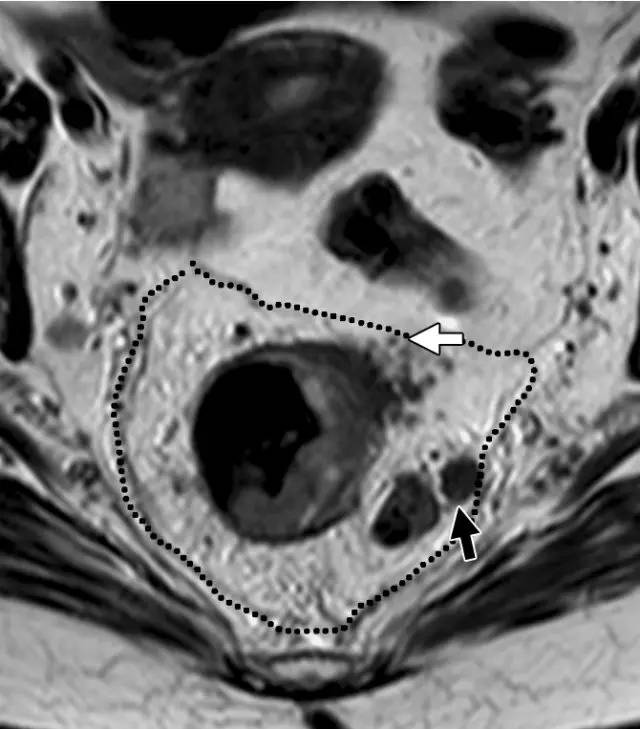

图 31 轴向 T2 加权图像报告 CRM 的距离。T3d 肿瘤局限于固有肌层内,肿瘤毗邻直肠系膜筋膜(箭头;肿瘤为 T2)。侵犯边界似乎是左后方(白色箭头),肿瘤的 CRM 评估为 5 mm。但有两个混合信号强度淋巴结(黑色箭头)邻接直肠,导致 CRM 为 0 mm。

图 32 轴向 T2 加权图像报告 CRM 的距离。T3c 肿瘤,靠近腹膜的 EMVI(白色箭头)和不规则信号强度淋巴结的 T3c 肿瘤,通过毗邻直肠系膜筋膜的淋巴结包膜(黑色箭头)肿瘤扩展(预测 CRM = 0 mm)。